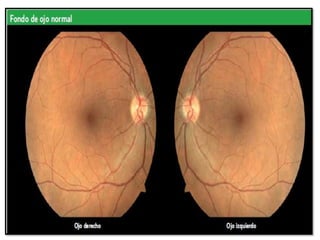

OFTALMOSCOPIA DEL FONDO DE OJO NORMAL

LAS ESTRUCTURAS DEL FONDO DE OJO QUE SE EXAMINAN SON:

PARÉNQUIMA RETINIANO:

PAPILA O DISCO ÓPTICO:

RETINA : membrana semitransparente

La COLORACIÓN ROJIZA que presenta se debe a

la tonalidad del EPITELIO PIGMENTARIO.

puede variar dependiendo de la raza, edad y color

de la piel.